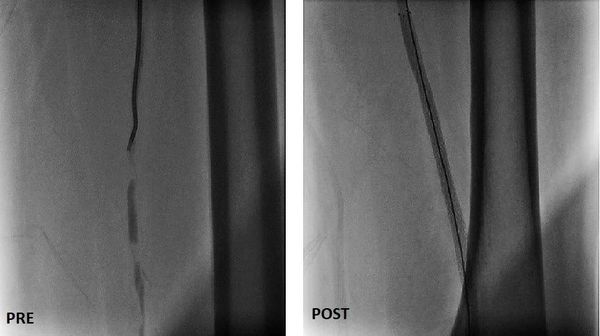

جراح أوعية دموية متخصص في علاج الوحمات الدموية للأطفال - انسداد الشرايين - قدم السكري والغرغرينا -علاج دوالي الساقين بالليزر

استشاري جراحة الأوعية الدموية و القسطرة التداخلية الطرفية